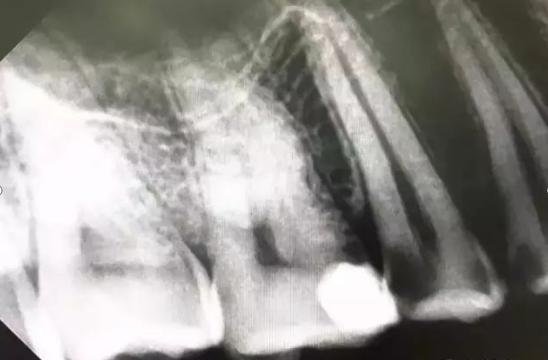

还有些龋坏位于两颗牙之间,临床上称之为邻面龋,表面上看起来完好无损,但一拍牙片,问题就暴露无遗。这样的龋坏起初可能只表现为食物嵌塞。

若不及时进行牙线清洁,定期检查治疗,就会逐渐出现食物嵌塞疼、冷热刺激疼等症状,此时牙缝间可能已形成了较深的龋坏。 02 、你以为不磨就可以补牙吗?